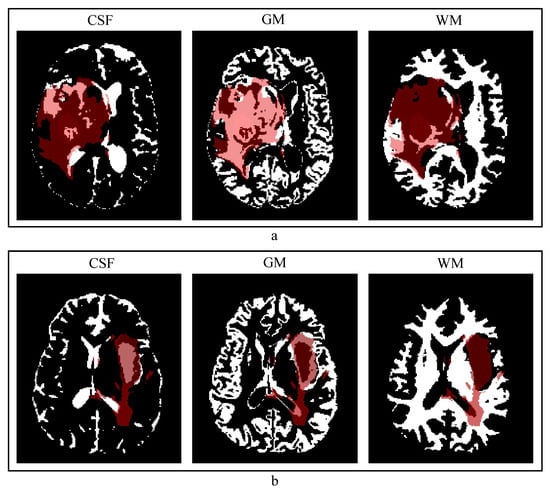

4.2. Quality of the Anatomical Contextual Information